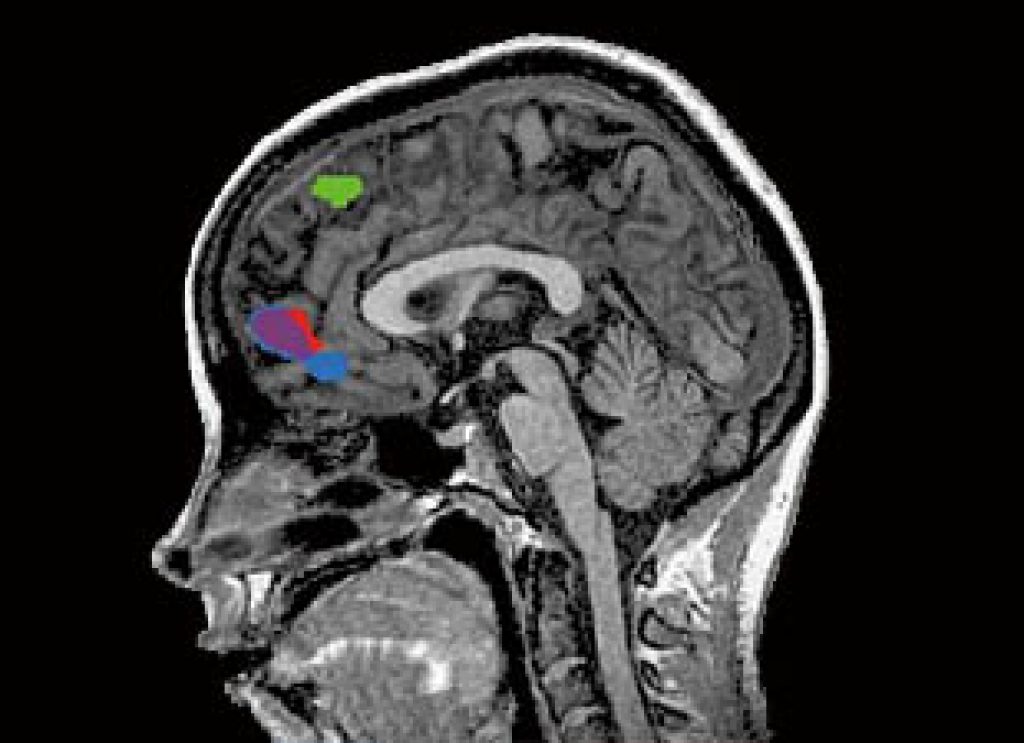

The authors found that humans simulate the decisions of other people using two brain signals encoded in the prefrontal cortex, an area responsible for higher cognition.

They found that the reward signal is processed in a part of the brain called the ventromedial prefrontal cortex. The action signal, on the other hand, was found in a separate brain area called the dorsomedial prefrontal cortex.